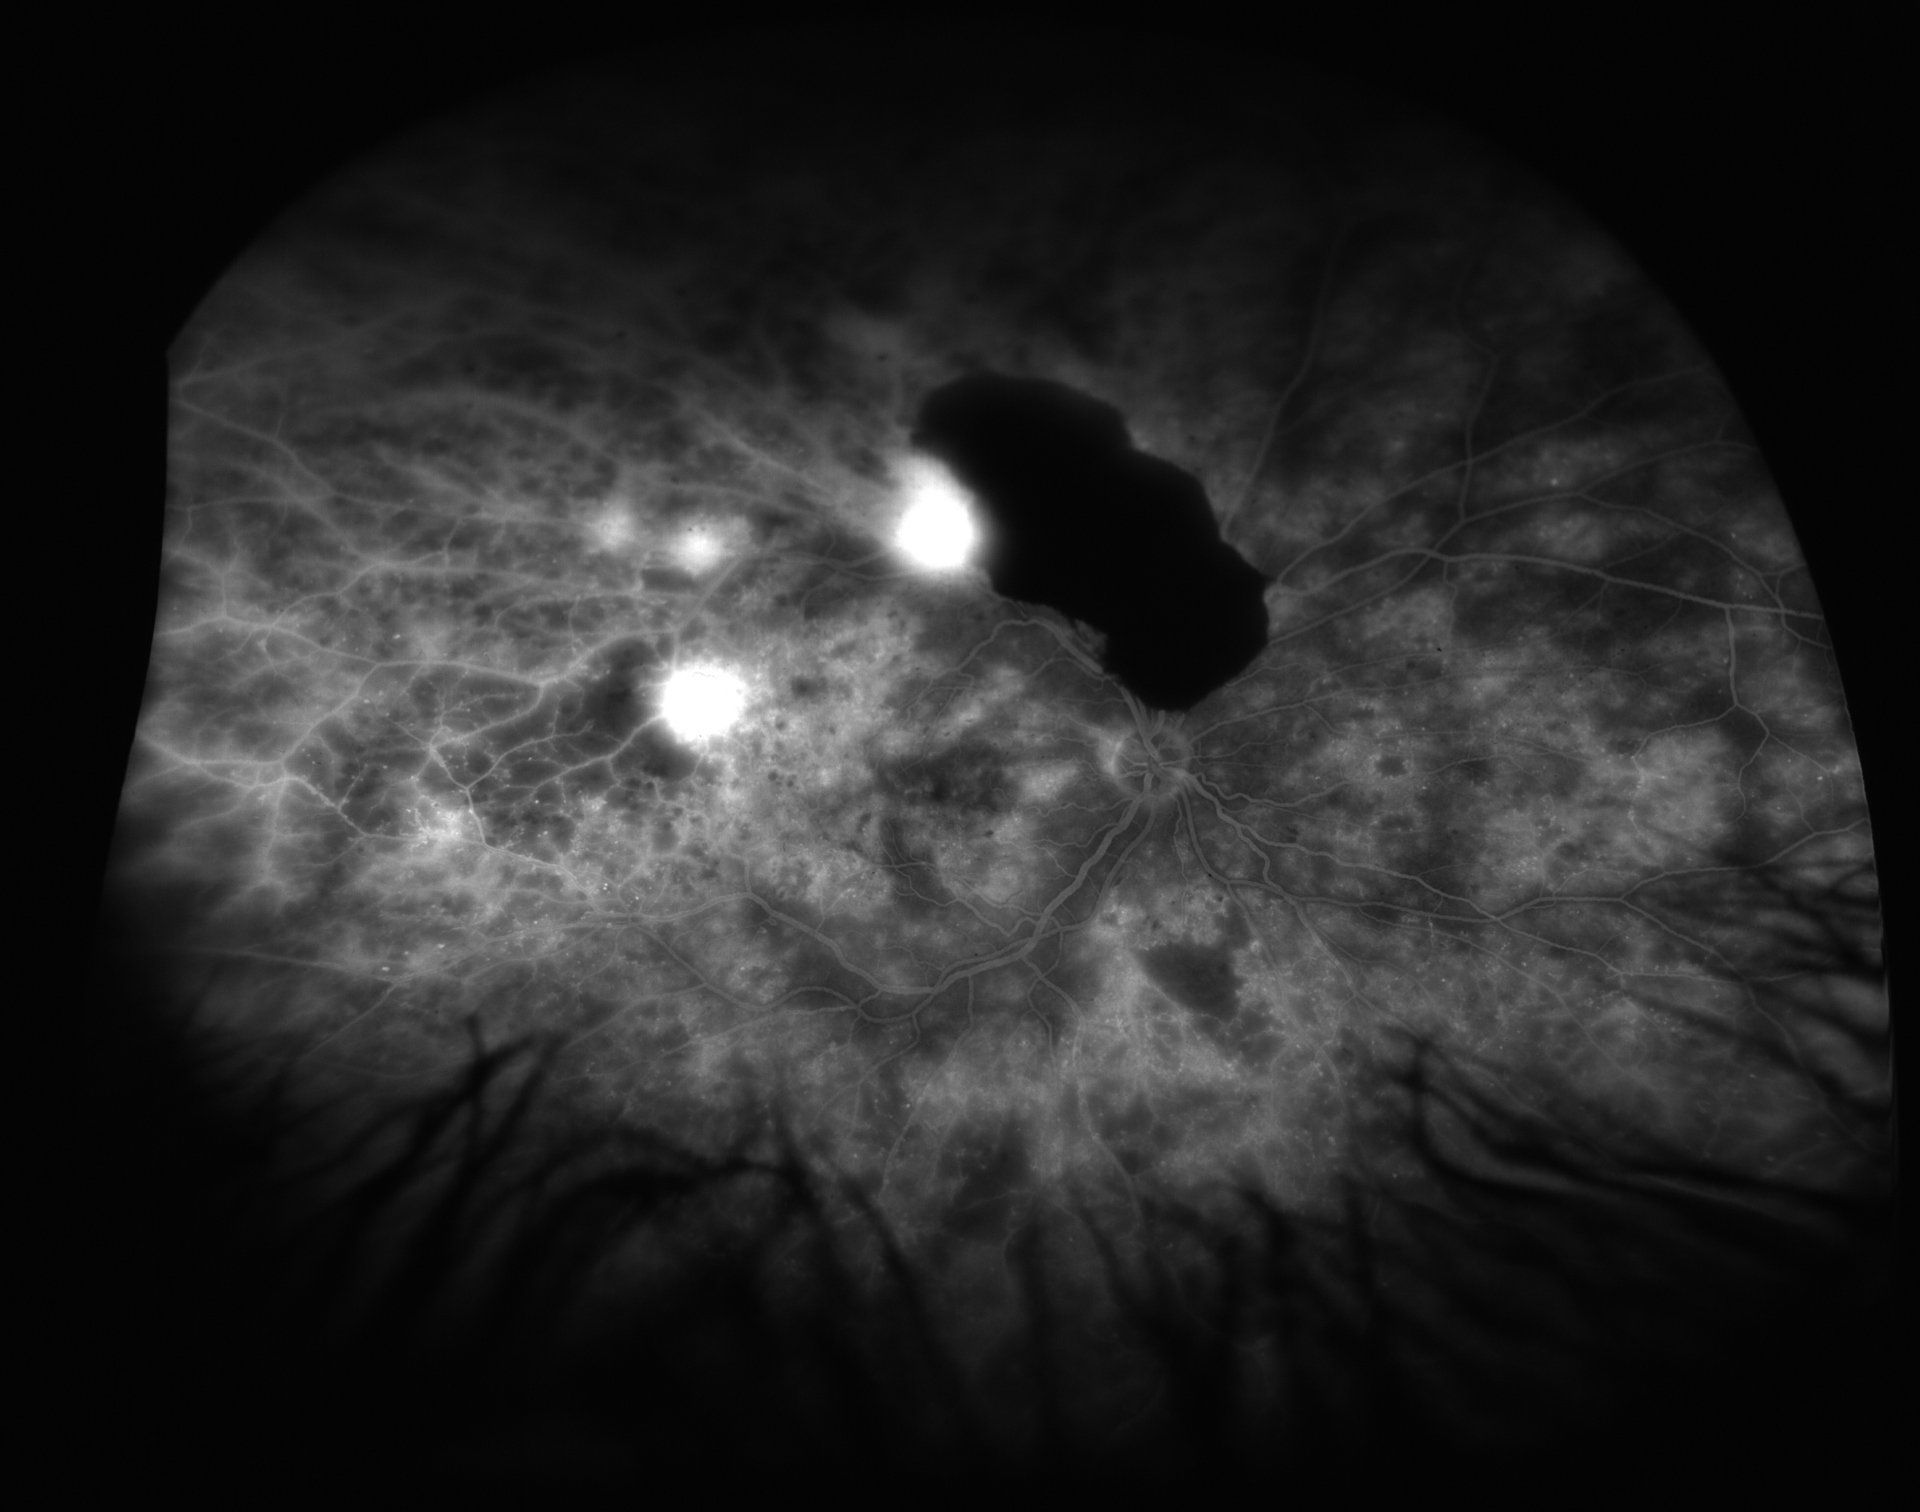

Write your caption hereButton

Write your caption hereButton